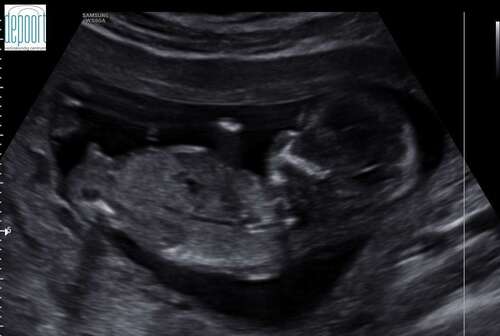

Nog een tweede foto. Ik ben hier 13w en 5dagen

💙